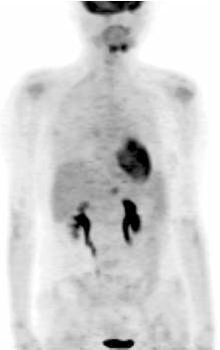

张国淳:目前对化疗效果的评价还有外周循环血肿瘤细胞(circulating tumor cells, CTC)检测这一手段。CTC检测已经被美国FDA批准为评价疗效的手段之一, 但尚未在中国正式上市。广东省人民医院乳腺科正在参与一项CTC检测用于转移性乳腺癌的多中心Ⅲ 期临床试验。因此, 该患者也加入了此研究。该患者开始一线治疗之前的CTC检测结果为185个/7.5 mL血, 而在2个周期后已经明显降低至92个/7.5 mL血。如果按照CTC检测的结果, 患者对XT方案的治疗是有效的, 不应该更换方案。因此, 我们为该患者制定了继续XT方案化疗的策略。在第4周期末时又进行了PET检查及CTC检测。PET结果显示:右侧乳腺结节、肝脏肿块局灶性葡萄糖代谢异常增高灶; 与前次PET影像比较, 原骨髓多发高代谢病灶明显减少, 葡萄糖代谢活性减低; 肝左叶转移灶缩小, 葡萄糖代谢活性减低, 提示化疗后转移瘤部分缓解, 见图3。而CTC检测的结果则显示:CTC数量为1个/7.5 mL血。因此, 在完成4个周期XT之后的疗效评价为部分缓解, 继续进行2个周期XT方案化疗。